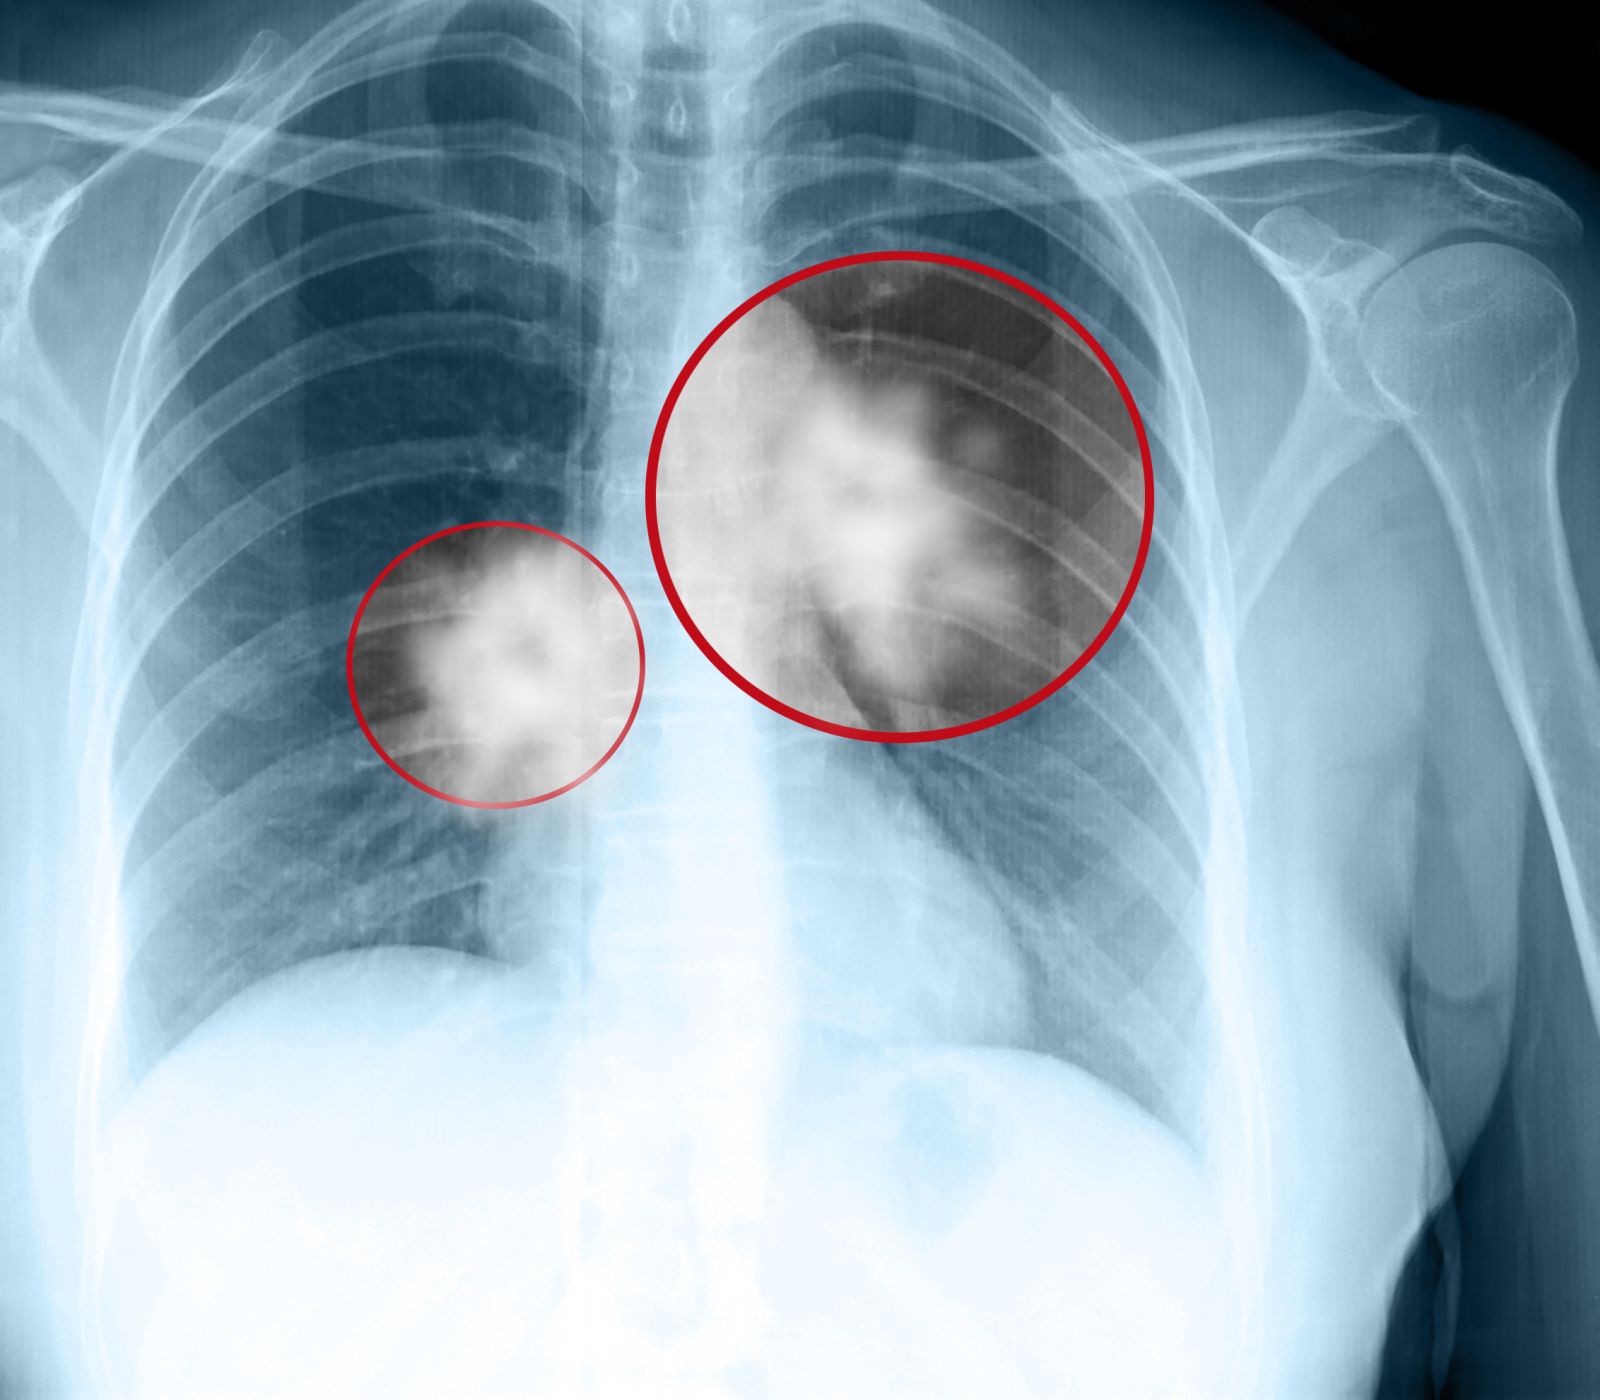

Triple treatment could keep lung cancer from coming back New Israeli approach stops lung cancer cells from developing resistance to chemotherapy in mice.